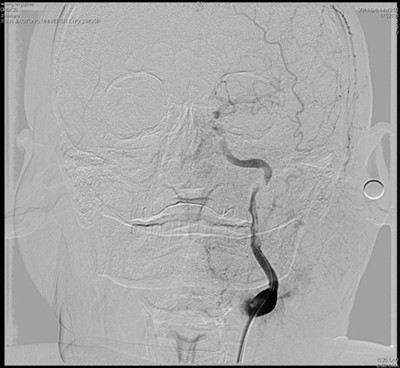

图1 正位片:左侧颈内动脉血管内可见混杂密度团块影,且重度狭窄

患者送入我院时意识模糊,右侧肢体完全不能移动,不能言语,我院神经内科按照脑梗死应急预案,通过急性脑梗死绿色通道立即行头颅CT排除脑出血。考虑脑梗死,但病灶尚未显示,有急诊动脉介入治疗的指证和时间。吴海琴主任和张桂莲副主任立即向家属谈病情并介绍介入治疗的利弊,同时展淑琴副主任医师和卜宁及孙宏主治医师指导完成术前各项准备工作并加用基础治疗。家属了解病情后签字同意介入治疗。吴海琴主任、张桂莲副主任、张茹副主任医师立即在祁小江技师、赵菊凤护士的配合下给患者行脑血管造影,造影见左侧颈内动脉内有异常混杂密度团块影,并局部重度狭窄,远端血管血供极差,考虑血栓形成所致狭窄。虑及动脉溶栓有可能使血栓脱落,栓塞远端血管,遂在保护伞的保护下给局部狭窄部位安放2枚支架,把血栓压住贴壁,使狭窄的颈内动脉基本恢复正常,远端血供恢复,患者意识清楚,右侧肢体能够在床头移动。此时距离患者发病仅4小时。今晨患者右侧肢体能够抬离床面并对抗阻力,能连续说出数个单词。